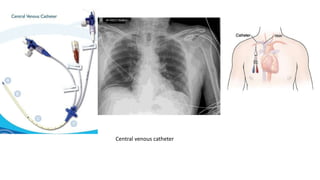

Placement of central lines.

• Central venous catheter (CVC)- These is advanced into the venecava

through veins . It facilitate the administration of long term drugs,

dialysis ,blood transfusion , drawing blood and monitoring central

venous pressure.

• Make sure to position patient and tube correctly in order to show

correct placement of catheter in radiograph .

• Avoid patient rotation .

Central venous catheter